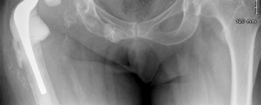

History of presenting complaint : Presents with a draining wound and well-fixed cementless components with a constrained liner due to absent abductor mechanism (Fig. 19.12). Treated with Prostalac and six weeks of IV antibiotics (Fig. 19.13). At the 6-week point, the patient sustained a ground level fall with an acetabular fracture and displacement of the acetabular Prostalac (Fig. 19.14).

Diagnosis : Treated MRSA infection of the right THA with acute acetabular fracture and patient now unable to mobilize due to pain (Fig. 19.14).